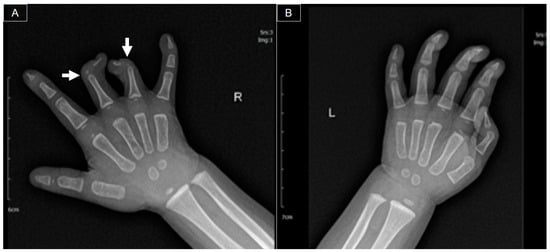

At 11 months old, she was initially brought to our orthopedic clinic due to a congenital deformity in her right hand. The physical examination revealed symbrachydactyly (short fingers that may be webbed or joined) and clinodactyly (fingers that curve to one side) in the right third and fourth fingers, along with a limited range of motion [1]. Stiffness was observed over the distal (DIP) and proximal (PIP) interphalangeal joints of the second and fifth fingers. The range of motion was preserved over the metacarpophalangeal (MCP) joints and the entire thumb. Radiography revealed hypoplasia of the middle phalanges and curvature in the coronal plane of the distal phalanges over the right third and fourth digits (Figure 1).

Figure 1. Bilateral hand X-rays ((A) right hand; (B) left hand) indicating hypoplasia in the middle phalanges and angulation deformities (arrows) in the distal phalanges of the right third and fourth fingers.